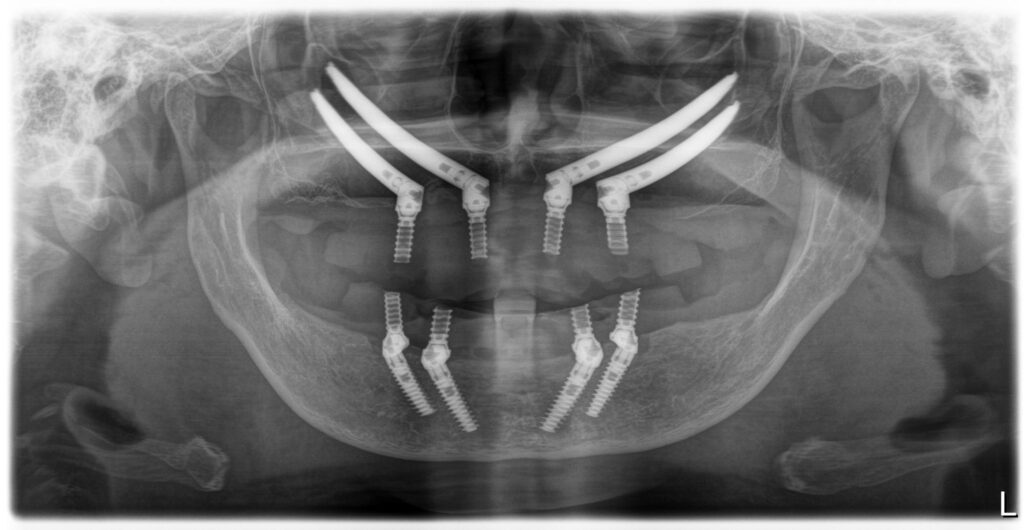

Bedrossianの分類より、ZoneⅠ〜Ⅲいずれにも十分な骨を認めないことから、Insufficient Boneと判断ができ、ノーマルインプラントは困難であることが考えられる。上顎はAll-on-4のためにはザイゴマインプラントが4本必要であることが考えられる。下顎は十分な歯槽骨量があることから、ノーマルインプラント4本を埋入することが可能であると考えられる。また、上顎のザイゴマインプラントの埋入に関しては、 ZAGA分類のType3とType4が混在しているため、ザイゴマインプラントが困難であることが予想される。